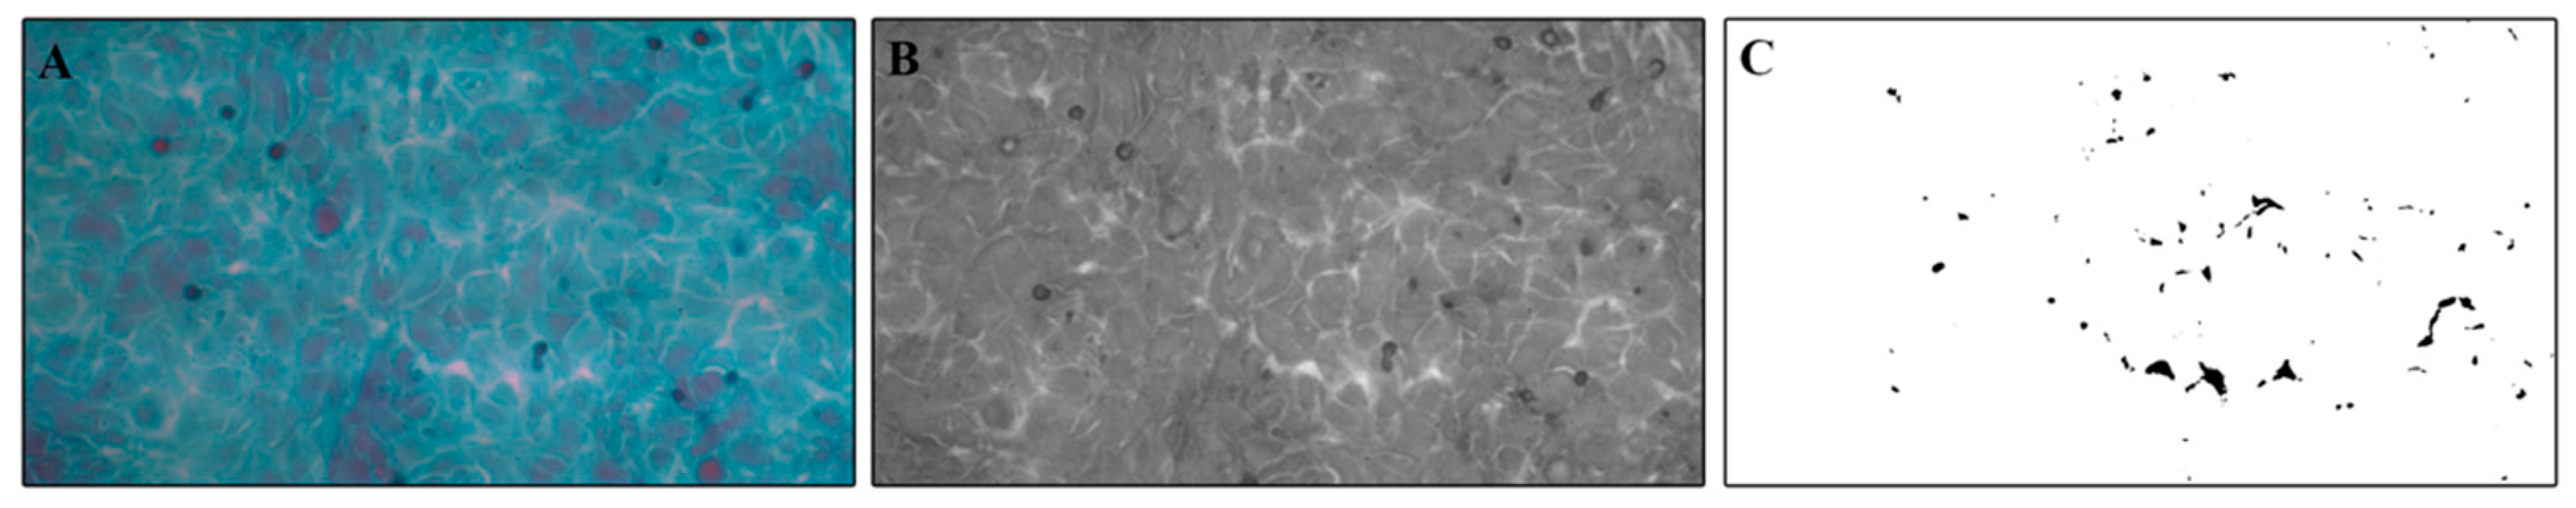

2.4. Papanicolaou Cytological Staining and Intercellular Spaces Evaluation

3.3. Evaluation of Intercellular Spaces